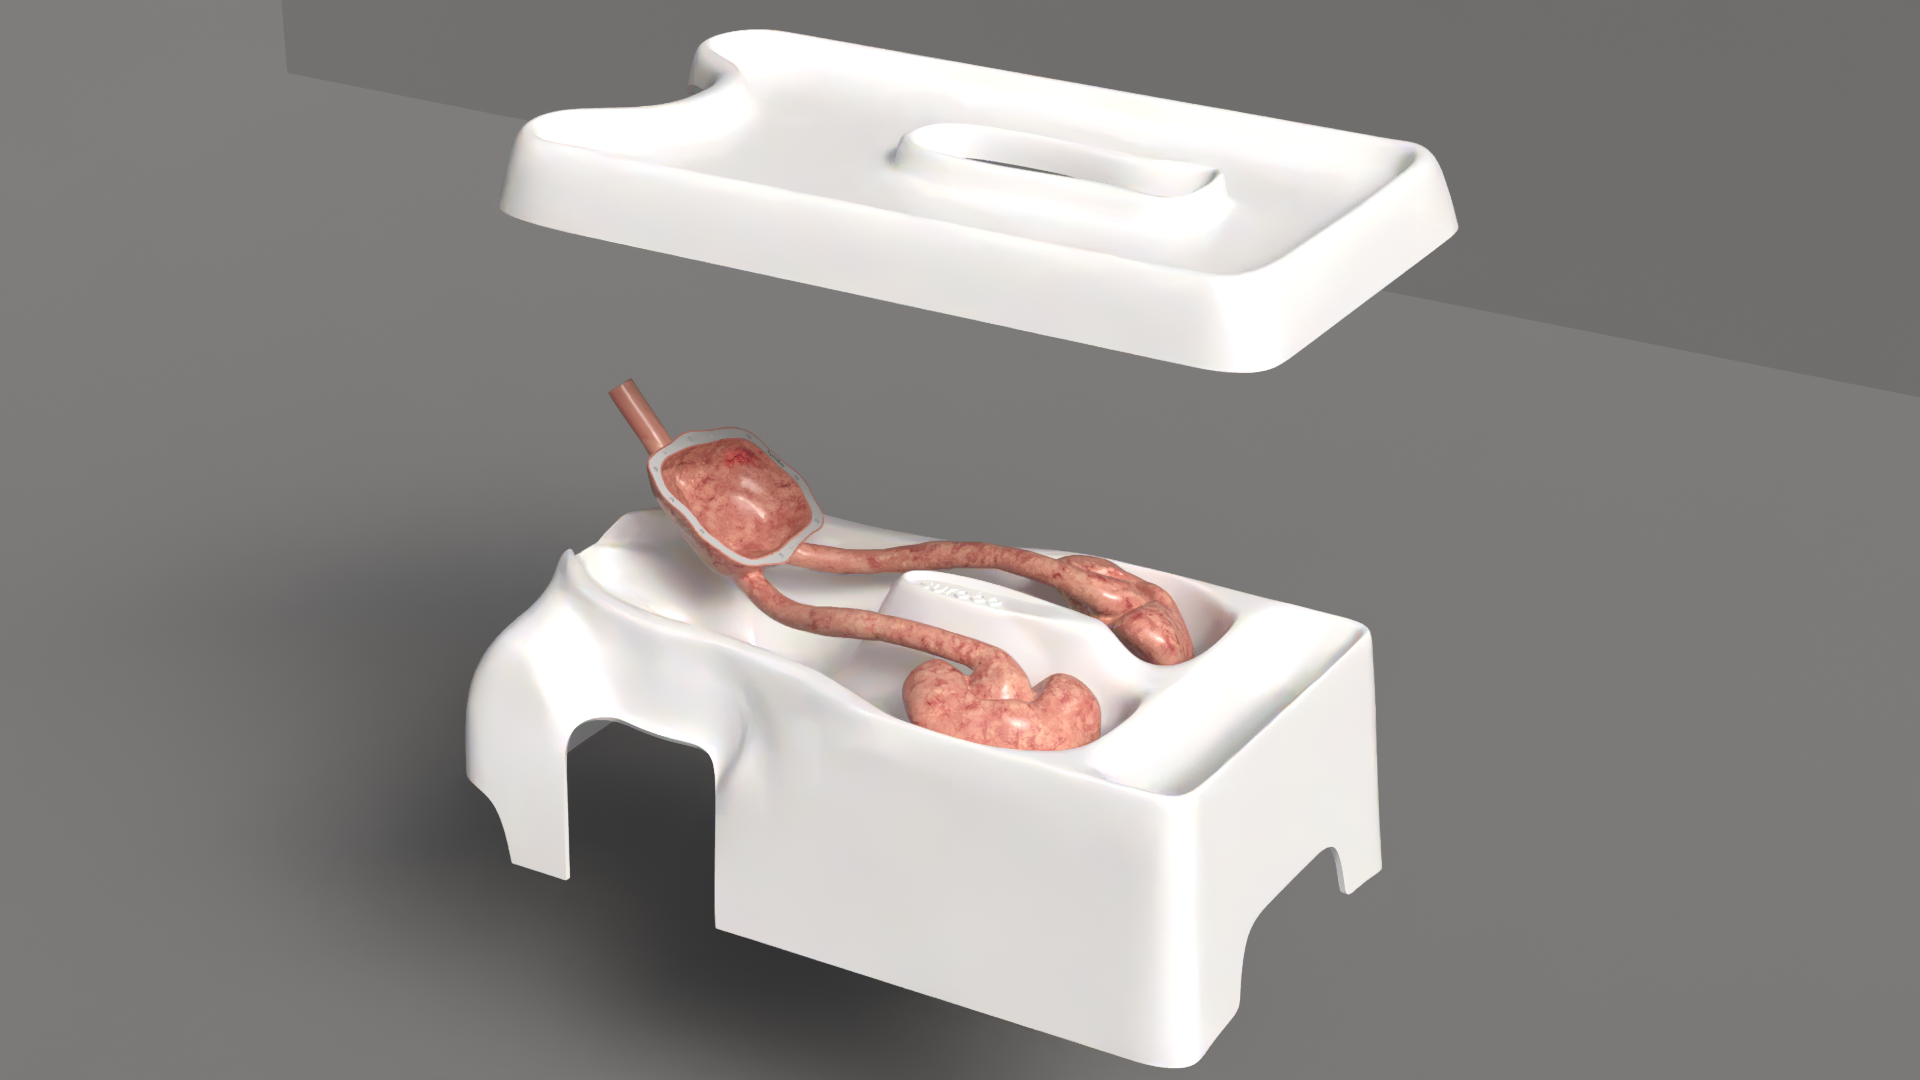

symu is an endo-urology simulator. It’s designed for ease of transport and use, and is housed in a cabin-sized wheeled case. The textured, resin-printed model is renowned for its strength and durability.

The urinary tract components are removable, and feature covers to facilitate the positioning of removable kidney stones or tumors. The model is supplied with dummy stones and removable magnetized tumors.